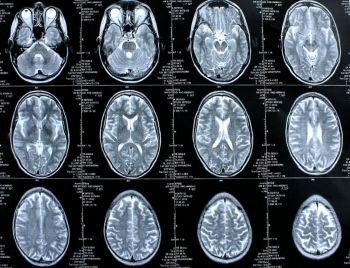

Die Magnetresonanztomographie (MRT), auch Kernspintomographie genannt, liefert mittels Magnetfeldern und Radiowellen eine detaillierte Darstellung von Organen bzw. krankhaften Organveränderungen und wird vor allem in der medizinischen Diagnostik eingesetzt.

Mit einer bestimmten Art der MRT, der Funktionellen Magnetresonanz-Tomografie (fMRT) kann man dem Gehirn sozusagen bei der „Arbeit“ zuschauen. Die fMRT ermöglicht es, Durchblutungsänderungen von Hirnarealen mit hoher räumlicher Auflösung zu beobachten, wenn Patienten zum Beispiel Aufgaben lösen oder Bilder betrachten.